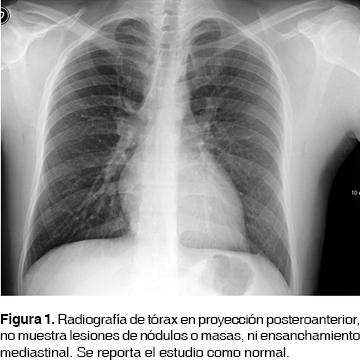

Paciente masculino de 37 años, con antecedentes de asma durante la infancia; presentó un neumotórax derecho espontáneo primario hace 15 años, tratado con colocación de sonda pleural por cuatro días, secundario a bulas congénitas. Hace cinco años funduplicatura de Nissen (360o) sin complicaciones. Previo a su ingreso al hospital presentó disnea de grandes a medianos esfuerzos, sibilancias audibles a distancia, motivo por el que se le realiza radiografía de tórax en proyección posteroanterior (figura 1), siendo reportada como normal; se inicia tratamiento con bromuro de ipatropio/salbutamol y ceftriaxona, con mejoría parcial del cuadro. A los tres días de haber iniciado el tratamiento presenta tos con escasos hemoptoicos intermitentes, situación por la que asiste a urgencias en donde se le realiza tomografía simple de tórax (figura 2) con presencia de una masa a nivel del bronquio principal derecho, así como presencia de adenomegalias mediastinales.